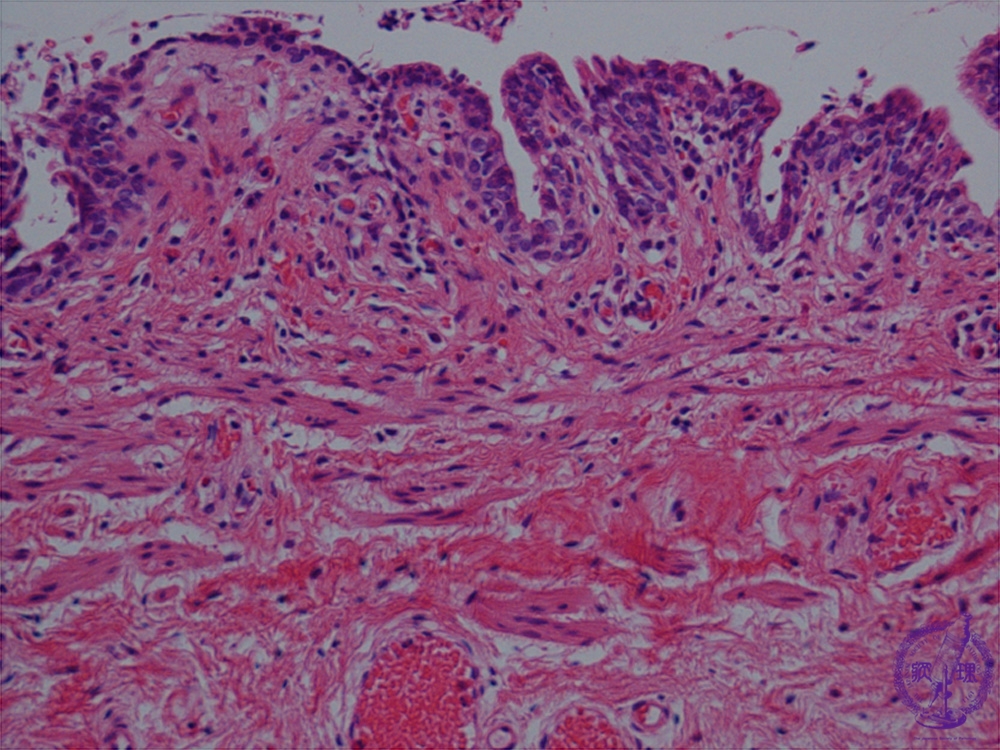

- (1)Hirschprung disease

Microscopic view: While nerve fibers are present (arrows), ganglion cells are not.